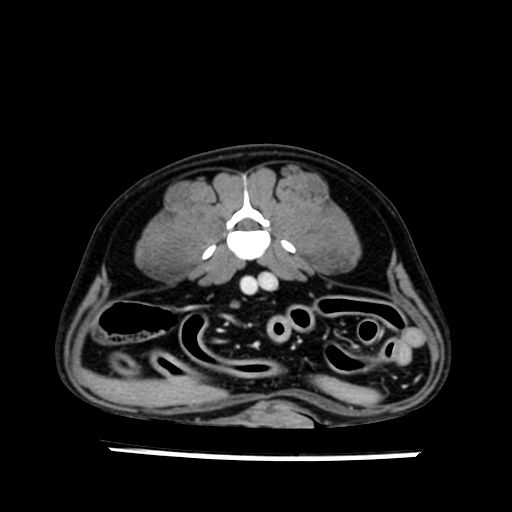

prescritto esame TAC

sequenza immagini limitata al fegato reni e surreni

le immagini ecografiche rispetto alla tac datano circa 7 mesi prima ,le surrenali sono normali nonostante il test acth sia risultato positivo .all’esame TAC dopo diversi mesi risultano aumentate armonicamente nel volume e si individua un forte sospetto di adenoma ipofisario .

sospetto adenoma ipofisario vs. meno probabilmente meningioma della base; intertiziopatia polmonare; lesione espansiva epatica, verosimilmente del lobo laterale sinistro, di sospetta natura neoplastica; lesioni spleniche di natura da definire; iperplasia/ipertrofia delle ghiandole surrenali, bilateralmente; vertebra di transizione del rachide toracico; tenosinovite cronica del muscolo bicipite brachiale di destra.